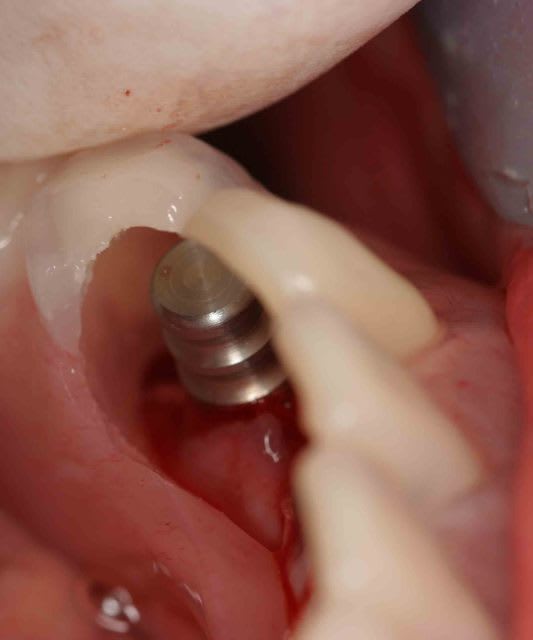

c'est çà qui te fais mal au coeur gaby?

Crête régularisée elgiow - Eugenol